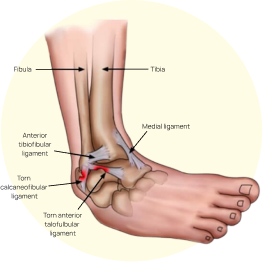

Occurs when the ligaments supporting the ankle stretch or tear due to sudden twisting or rolling of the foot, leading to pain, swelling, bruising, and difficulty walking or bearing weight on the affected ankle.

Ankle pain results from sprains, where ligaments stretch or tear due to twisting motions during activities or on uneven surfaces, leading to pain, swelling, and difficulty bearing weight.

Traumatic injuries like ligament tears (e.g., ACL tears in the knee) or fractures in the ankle from falls or impacts cause immediate pain, swelling, instability, and reduced joint movement, often requiring immobilization and rehabilitation or surgery.